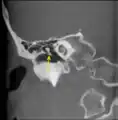

CT imagem de martelo.